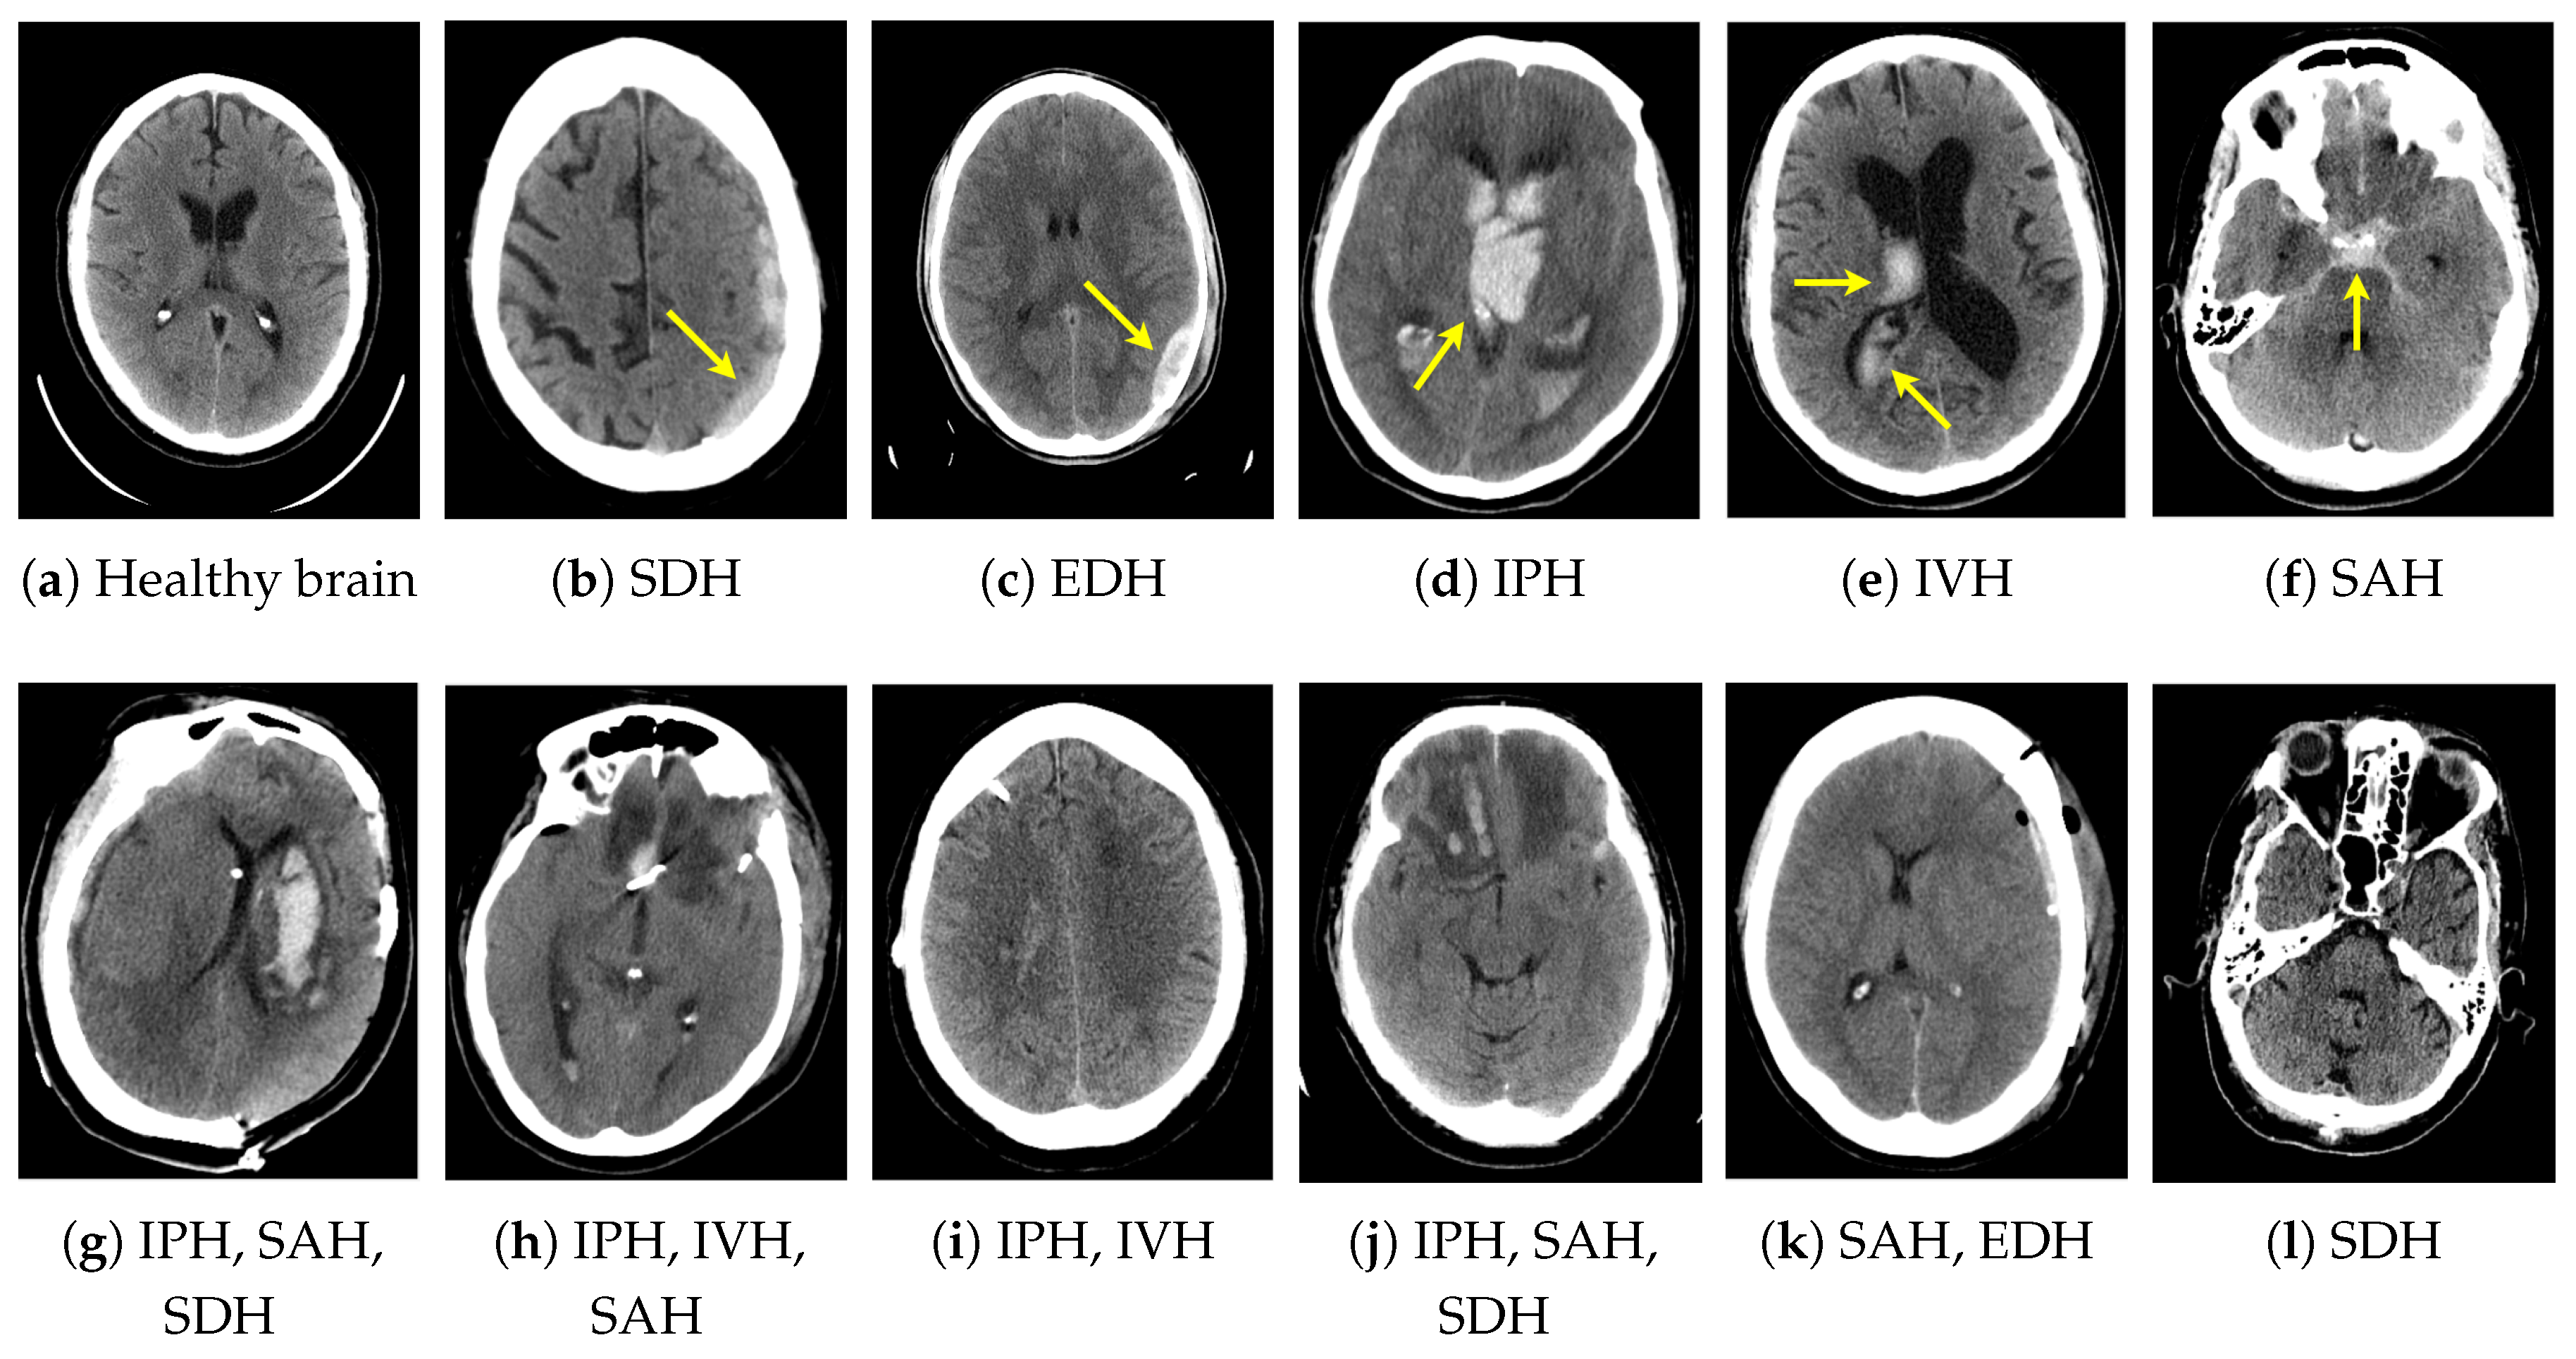

Depending on the brain’s anatomic site of bleeding, several ICH subtypes can be distinguished (Figure 1). Subdural hemorrhage (SDH) refers to bleeding between the dura and the arachnoid, whereas the epidural subtype (EDH) involves bleeding between the dura and the bone. Both frequently result from traumatic injuries. Intraparenchymal hemorrhage (IPH) is bleeding within the area of brain parenchyma. A hemorrhage inside the ventricular system is known as intraventricular (IVH). Finally, blood within the subarachnoid space indicates subarachnoid hemorrhage (SAH) [1,5]. One of the leading causes of SAH is a ruptured cerebral aneurysm [3,4]. Hemorrhage detection and classification are challenging due to similarities between the various ICH subtypes (e.g., SDH vs. EDH) and subtle differences between healthy and bleeding tissues. These are barely noticeable to the inexperienced observer. Figure 1 presents examples of selected CT slices featuring the physiological brain appearance and ICH subtypes under consideration.

Figure 1.

Sample non-contrast computed tomography (CT) slices with various intracranial hemorrhage (ICH) subtypes in the top row (a–f). Yellow arrows indicate the areas of hemorrhage. Complex cases are shown in the bottom row: combinations of multiple ICH subtypes simultaneously (g–k) or barely visible ICH symptoms (l).